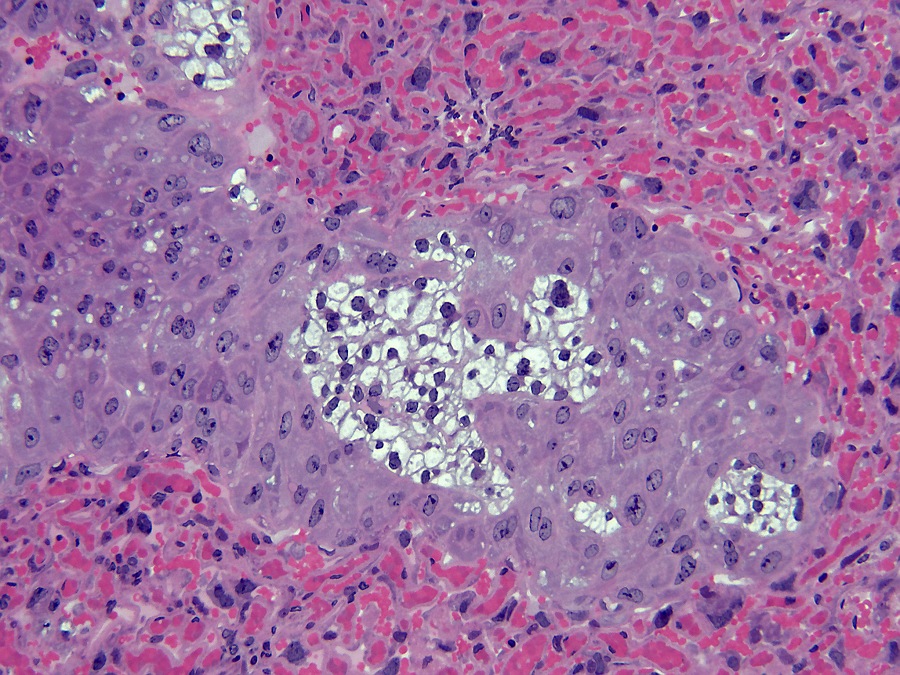

De muis heeft een hemochoriale placenta waarbij maternaal bloed in contact staat met foetaal chorion via een labyrintische laag (mensen hebben een vergelijkbaar type placentatie). De placenta bestaat uit maternale en embryonale lagen. De van het moederdier afkomstige laag is de decidua, die zich ontwikkelt uit het endometrium. De decidua bestaat uit twee delen: de decidua basalis en de decidua capsularis. De basalis heeft een rijk vasculair netwerk en bestaat uit losjes aanhangende onregelmatige grote vacuolate cellen met verschillend gevormde kernen van verschillende grootte.

De decidua wordt van de embryonale labyrintische zone gescheiden door de junctionele zone. De junctionele zone bevat maternale bloedvaten (veneuze drainage), trofoblastreuscellen en spongiotrofoblastcellen. Trofoblastcellen zijn over het algemeen erg groot met bizar gevormde of meervoudige kernen. Reusceltrofoblasten zijn, zoals hun naam al zegt, erg groot - tot 100 µm in diameter en bevinden zich het dichtst bij de decidua. Spongiotrofoblasten zijn fagocytisch[6] en kunnen gefagocytiseerde erytrocyten bevatten en bevinden zich dichter bij de labyrintische zone. De labyrintische zone bestaat uit nauw tegenover elkaar liggende foetale en maternale bloedkanalen. De foetale bloedkanalen zijn bekleed met dunne endotheelcellen en bevatten grote onrijpe gekerfde rode bloedcellen, terwijl de maternale bloedkanalen bekleed zijn met grote labyrintische trofoblastcellen.

Reusceltrofoblastcellen[3] zijn betrokken bij de modulatie van de maternale vasculatuur van de decidua en ze produceren verschillende placenta-specifieke hormonen die lijken op het hypofysehormoon prolactine[6]. Dit zijn onder andere Pl-1, Pl-2 (placentalactogeen) en proliferine, die uitsluitend door reuscellen worden uitgescheiden. Pl-1 en Pl-2 moduleren de activiteit van de eierstokken door de productie van luteaal progesteron te stimuleren, wat essentieel is voor het behoud van de zwangerschap. Bovendien zijn Pl-1 en Pl-2 betrokken bij de controle van de borstklierontwikkeling.